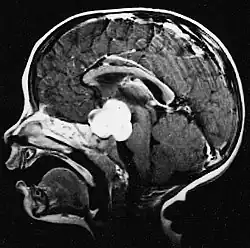

Pilocytic astrocytoma (and its variant pilomyxoid astrocytoma) is a brain tumor that occurs most commonly in children and young adults (in the first 20 years of life). They usually arise in the cerebellum, near the brainstem, in the hypothalamic region, or the optic chiasm, but they may occur in any area where astrocytes are present, including the cerebral hemispheres and the spinal cord. These tumors are usually slow growing and benign, corresponding to WHO malignancy grade 1.[1]

Pilocytic astrocytomas are often cystic tumors, and, if solid, tend to be well-circumscribed.

Usually – depending on the interview of the patient and after a clinical exam which includes a neurological exam and an ophthalmological exam – a CT scan and/or an MRI scan will be performed to confirm the presence of a tumor. They are usually easily distinguishable from normal brain structures using these imaging techniques. A special dye may be injected into a vein before these scans to provide contrast and make tumors easier to identify. Pilocytic astrocytomas are typically clearly visible on such scans, but it is often difficult to say based on imaging alone what type of tumor is present.